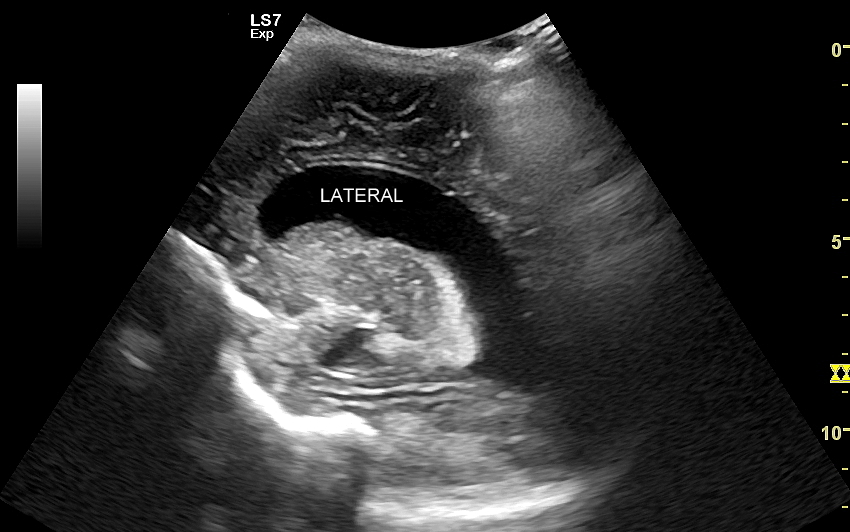

USG główki to podstawowa metoda diagnostyczna mózgu i struktur okołomózgowych u wcześniaków, noworodków i niemowląt. Badanie jest bezbolesne i nieryzykowne w porównaniu do rezonansu magnetycznego, podczas którego dziecko poddawane jest znieczuleniu ogólnemu. Przeprowadzenie szerokiego i szczegółowego badania USG główki jest możliwe aż do momentu zarośnięcia ciemiączka, czyli chrzęstnej struktury w pokrywie czaszki. Ze względu na cienką kość skroniową czaszki dziecka w późniejszym okresie możliwa jest wciąż częściowa ocena mózgowia w badaniu USG. Ambulatoryjne badanie USG przezciemiączkowe zwykle zalecane jest przez neonatologa, pediatrę lub neurologa dziecięcego w celu oceny mózgu wcześniaków, dzieci z małą masą urodzeniową, dzieci po epizodzie niedotlenienia lub krwawienia wewnątrzczaszkowego w trakcie porodu lub okresu noworodkowego, a także w przypadku wystąpienia drgawek, podejrzenia wady układu nerwowego, np. wodogłowia.

W USG główki dziecka oceniane są struktury wewnątrzczaszkowe, tj. mózg wraz z jego układem komór wewnętrznych, sploty naczyniówkowe, istota biała mózgu i obszary jąder podstawy mózgu, morfologia zakrętów i bruzd mózgowia, przestrzeń przymózgowa, a w trybach dopplerowskich wybrane naczynia tętnicze i żylne mózgu, w tym zatoki żylne. Oceniane są również cechy ciśnienia śródczaszkowego. W opisie badania podawane są również wymagane przez neurologa tzw. wskaźniki komorowe oraz wymiary wybranych struktur.